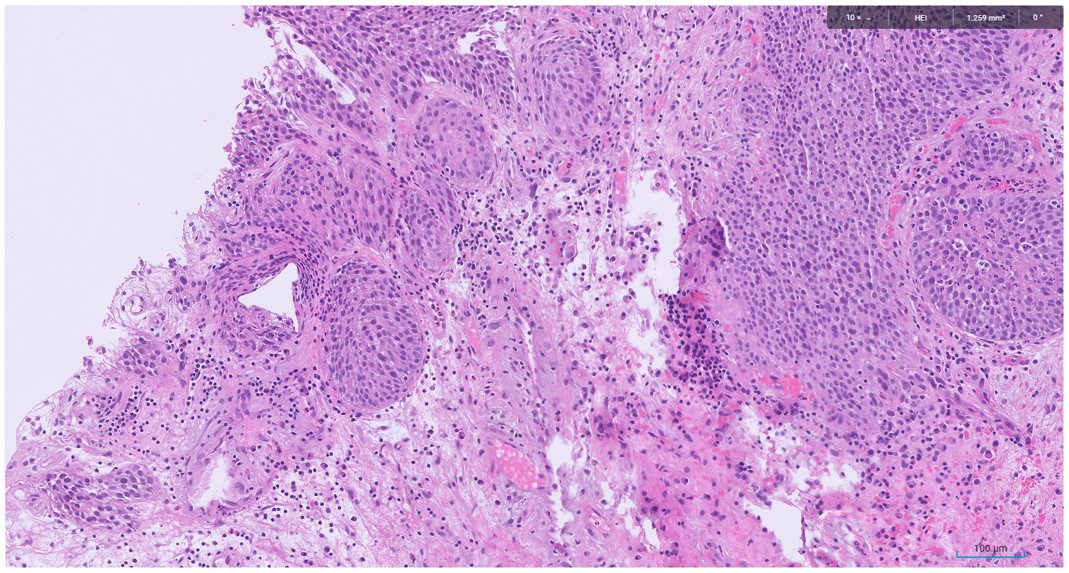

Microscopic image possibly detecting cancerous areas in human tissue

What is the most likely diagnosis?

1. Radiation cystitis

2. Cystitis cystica

3. Invasive urothelial carcinoma

4. carcinoma in situ

Radiation cystitis